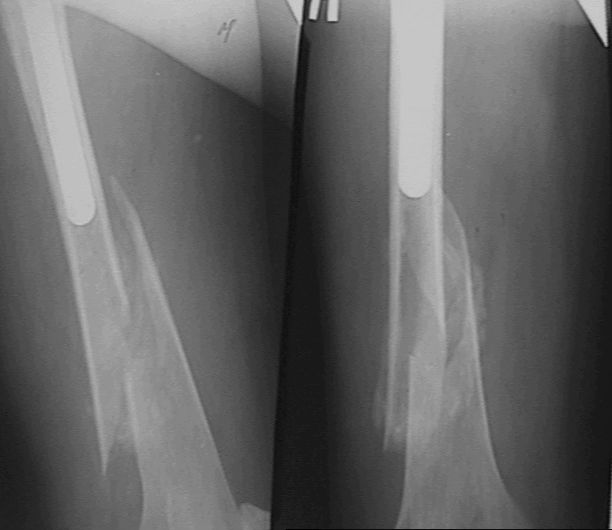

Больной оперирован в конце марта 2003 НИИТО г. Новосибирск. Не замечен перелом бедра р-ма 1.- 2 . (сделанных в НИИТО). Больному рекомендовали ходить приступая на конечность, отмечает усиление болей, появление укорочения.На контрольных рентгенограммах 19.05.03 рис 3 имеется перелом бедра со смещением, появлением периостальной мозоли. Больной ходит на костылях, приступая на конечность. Сгибание в т\б суставе 90 гр , сгибание в коленном суставе до 90 гр в положении стоя на костылях.Есть несколько вариантов.1. Провести открытую репозицию фиксацию пластиной с проведением винтов на уровне ножки протеза через кортикальный слой.2.Провести открытую репозицию фиксацию винтами с межфрагментарной компрессией. Думаем, как выполнить репозицию перелома по длине.3. Наложить кокситную повязку до окончательного сращения перелома4. Провести скелетное вытяжение репозицию.Сергей ЗыряновНовосибирская область г. Куйбышев ЦРБ

Рис-2 сделаны в НИИто через неделю после операции